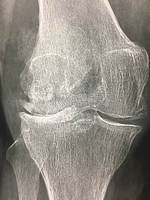

Nous avons vu que des jambes très arquées peuvent être une cause logique d'arthrose interne, comme sur la radio (genou droit vu de face).

Il est possible, chirurgicalement, de modifier l'axe du membre inférieur : l'idée est de modifier un petit peu l'axe dans l'autre sens : en passant par exemple, d'un varus à un petit valgus, pour soulager le compartiment interne usé, en appuyant plutôt sur le compartiment sain, externe. Cette opération ne concerne que les jeunes adultes autour de 40-50 ans.

L'ostéotomie consiste à couper un des deux os tibia ou fémur pour modifier l'angulation de la jambe, favorisant ainsi l'appui sur l'autre cöté (sain) du genou.

Déformation de l'articulation

La déformation de l'articulation est très lente. Le varus ou le valgus initial va augmenter petit à petit. Cette déformation n'est pas forcément gènante (en dehors de l'esthétique), si le genou garde sa mobilité. Un varus important est beaucoup mieux toléré qu'un valgus équivalent.

Elle entraine l'usure prédominante du compartiment en charge (interne pour le varus et externe pour le valgus). L'usure augmente la déformation et la pression sur le compartiment concerné.

La déformation en valgus avec une déformation en X, est beaucoup moins bien tolérée que la déformation en varus.